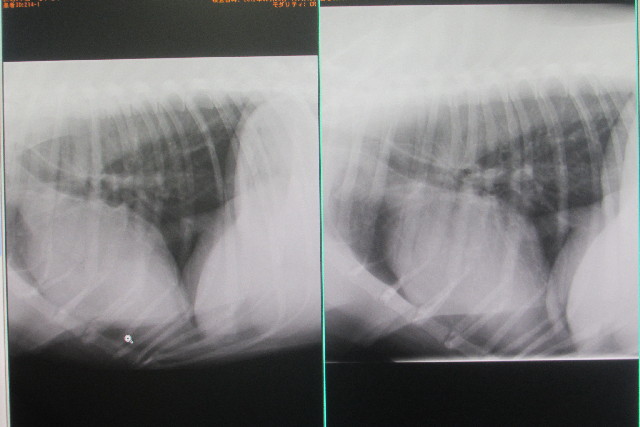

左が本日。右は2011年8月5日のレントゲン画像です。

触診では脾臓が腫れている感じでしたが、レントゲン上では問題なし。

心臓が細い感じがしたが、2011年の8月5日と比較して問題なし。

でも、老猫のように心臓が寝ているそうです。

GRは急に心臓が拡張してしまったり多いそうです。(肥大とはちがう。肥大は皮が厚くなる)